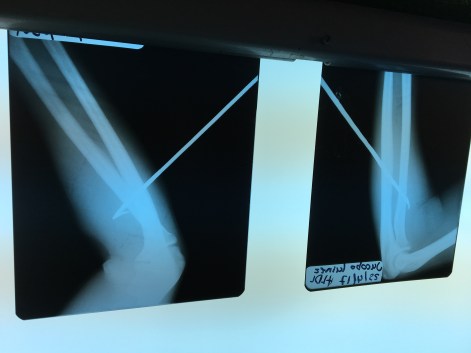

As Dr. Peter and I have discussed, the most dangerous creature out in the Carribean Sea is… us!—Humans. This guy was shot in the arm by a speargun, wielded by his buddy. Oopsie-daisy!